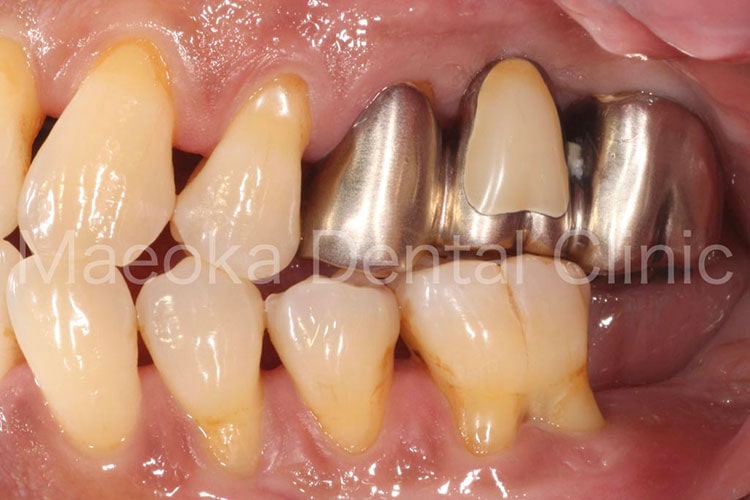

治療前(右側方面)

治療後(右側方面)

治療前(左側方面)

治療の詳細解説

治療内容

• メタルセラミックス(4本)

• ゴールドクラウン(1本)

• コンポジットレジン修復

• Extrusion処置

• 歯髄温存処置

概算治療費 約98万円

治療期間 約2年